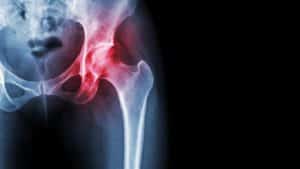

If you struggle with pain and stiffness in one or both hips, do you know what’s causing it? Is it arthritis or an inflammatory condition called bursitis? Here’s how your orthopedic surgeon in the Bismarck, ND, area can help you differentiate between the two conditions and what can be done to treat the discomfort. The…